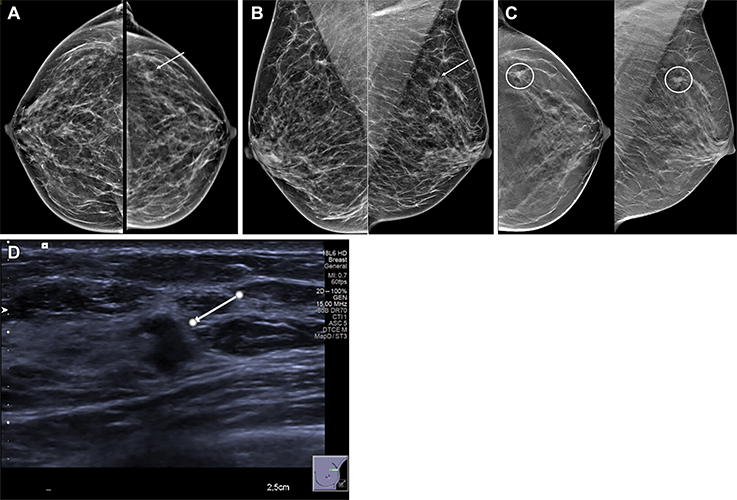

Images in a 54-year-old woman show a palpable lump in the right breast and an irregular mass in the left breast. Mammographic evaluation of the right breast was normal. (A, B) Craniocaudal (A) and mediolateral oblique (B) views of synthesized mammograms and (C) tomosynthesis image in craniocaudal and mediolateral oblique view of the left breast show an architectural distortion with mass (arrow in A and B, circles in C). (D) Targeted US scan at the site of the incidental finding shows an 8-mm hypoechogenic irregular solid mass with indistinct margins (arrow). US-guided biopsy showed invasive ductal carcinoma, grade I.